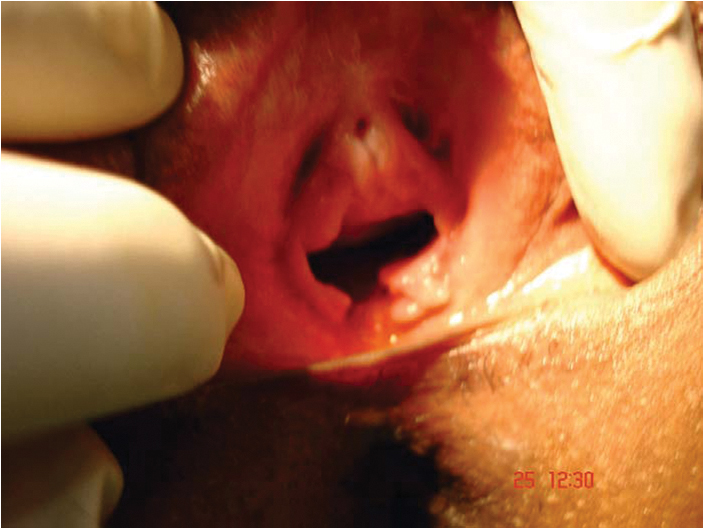

Figure 1: Ruptured hymen showing remnants.

Figure 2: Completed hymenoplasty.

In an ideal world, surgical training should be provided to gynaecologists and plastic surgeons to perform hymenoplasty safely and effectively (Figures 1-2). The hymenoplasty procedure can be combined with labial trimming (labial hypertrophy being a mark of frequent sexual intercourse), vaginal tightening and clitoral dehooding (Figure 3). Hymenoplasty should not be trivialised as a simple, risk-free procedure that can be done by any medical practitioner. Legalising hymenoplasty can also put a curb on errant practitioners performing hymenoplasty in back door clinics in unsanitary conditions. The complications such as vaginal stricture, fistulas, infection and bowel perforation that may arise from hymen reconstruction are all real and cannot be downplayed. Technical expertise and proper surgical training would be needed for a seemingly simple procedure such as hymenoplasty. Patient autonomy and confidentiality has to be strictly maintained in all instances.

The authors would like to thank Dr Vishwa Prakash of Safdarjung, New Delhi for supplying his pictures (Figures 1-2) for use in this publication.